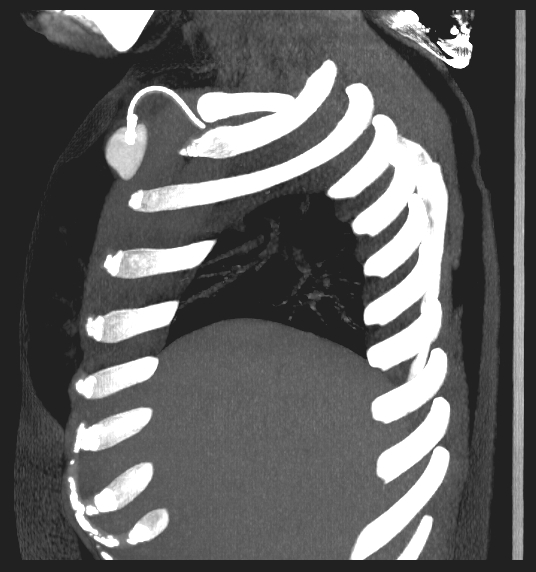

A twenty nine years old lady diagnosed as Carcinoma left breast underwent breast conservation surgery (pT2N2aM0, ER positive PR positive Her 2 neu positive) and presented for adjuvant chemotherapy. She was planned for adjuvant chemotherapy, radiotherapy and hormonal therapy as per standard guidelines. Chemoport reservoir was placed in the chest wall – right infraclavicular fossa and chemoport catheter was placed in the right subclavian vein. Post-procedure chest x ray revealed proper placement of the chemoport. She underwent first cycle of adjuvant chemotherapy with Docetaxel, Carboplatin and Trastuzumab without any complications. When she presented for second cycle (45 days after chemoport insertion), she was asymptomatic. However, there was no backflow of blood from the chemoport reservoir. Chest X ray revealed fragmentation and embolization of chemoport catheter. ECG showed normal sinus rhythm. Non Contrast CT scan chest was done, which revealed that the distal fragment of chemoport catheter had embolized to left pulmonary artery lower lobar branch, having migrated across the right atrium, right ventricle, main pulmonary artery and its left branch (Figure 1). After informed consent, retrieval of distal fragment of chemoport catheter was done in cath lab under local anesthesia under fluoroscopic guidance by Interventional Radiology team. It was retrieved from left pulmonary artery lower lobar branch in a procedure lasting forty minutes. The right femoral vein was punctured, 10 Fr Cordis sheath was introduced into the femoral vein, left pulmonary artery was cannulated using cobra 5 Fr catheter and then it was exchanged with snare over the guide wire. The left posterior inferior branch of pulmonary artery was selectively cannulated using Terumo guide wire and Cobra catheter. The tip of the foreign body was snared using Sequre snare system (4Fr, 10mm) and pulled through the pulmonary artery (Figure 2). The length of the catheter fragment was 4cm (Figure 3-9). The next day, chemoport reservoir and the proximal fragment of chemoport catheter was retrieved by surgery under local anesthesia. Patient tolerated both procedures well and was discharged on the third day.

Figure 3 MIP image sagittal view NCCT Chest showing chemoport reservoir in the chest wall.